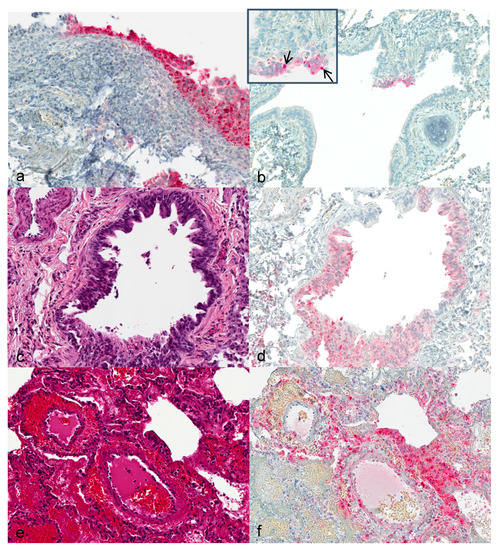

3.3. Histopathology and Immunohistochemistry

3.4. Transmission Electron Microscopy